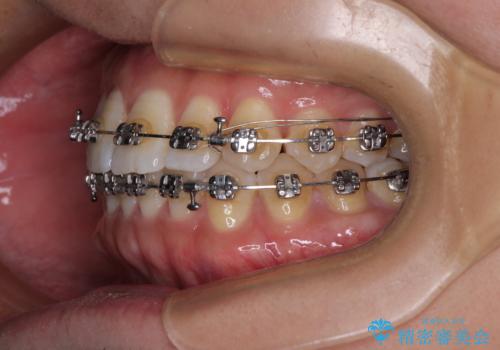

- メタルブラケット

- 1年4ヶ月

- 前歯のデコボコを気にして来院された患者様です。

インビザラインによるマウスピース矯正も適用となる歯列でしたが、できる限り自己管理の煩わしさのない状態で治したいとのことで、ワイヤー装置にて矯正治療を行うこととしました。

予定していた期間より長くかかりましたが、1年強できれいな歯列に仕上がりました。